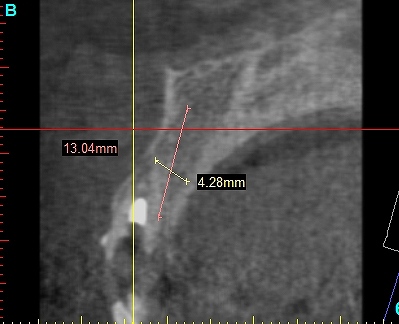

抜歯を行いました

即時インプラント埋入を行っています

術前の審査になります